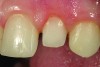

CL-II

CL-II deals with minimally invasive or modified prep-less veneers (Figure 4). Addition veneers also may fall in this classification. This category should exhibit 80% to 95% volume of remaining enamel, 10% to 20% exposed dentin, and up to 0.5 mm of reduction (Figure 5 and Figure 6). Ideally, CL-II veneers would have complete enamel periphery, but may involve a small zone on the gingival margin consisting of dentin to clearly establish the restoration margins (Figure 7).52 Additionally, 5% to 15% of dentin may be exposed on any facial surface (ie, mesial, distal, or gingival), depending on veneer rotation (Figure 8). To complete a CL-II preparation, a bis-acrylic preparation guide, as previously described, can be used.

Fig 5. Photograph of a minimally invasive or modified prepless Class II veneer preparation design.

Figure 5